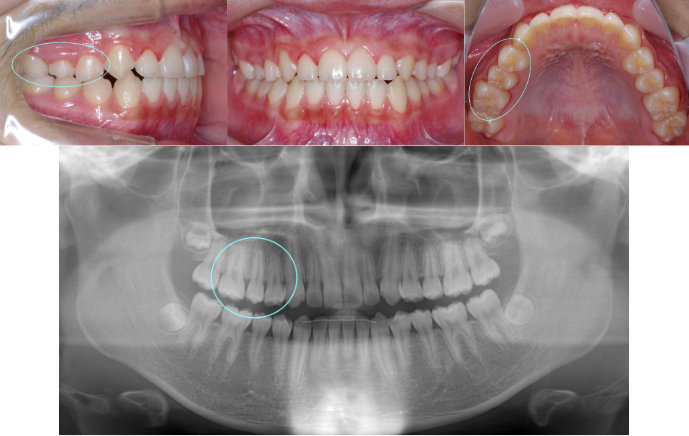

| Case1 |

| 出っ歯 |

| <治療前> |

| <治療後> |

| 主訴 |

前歯が出ている |

| 診断名 |

上顎前突 |

| 年齢 |

8歳 |

| 使用装置 |

マルチブラケット装置 |

| 抜歯部位 |

永久歯の抜歯は無し |

| 治療期間 |

2年4か月 |

| 治療費概算 |

検査・診断料:5万円+税 装置・技術料:25万円+税 おおよそ1か月ごとの処置・管理料:5,000円+税 保定装置料:5万円+税 |

| リスク・副作用 |

う蝕 歯根吸収 |